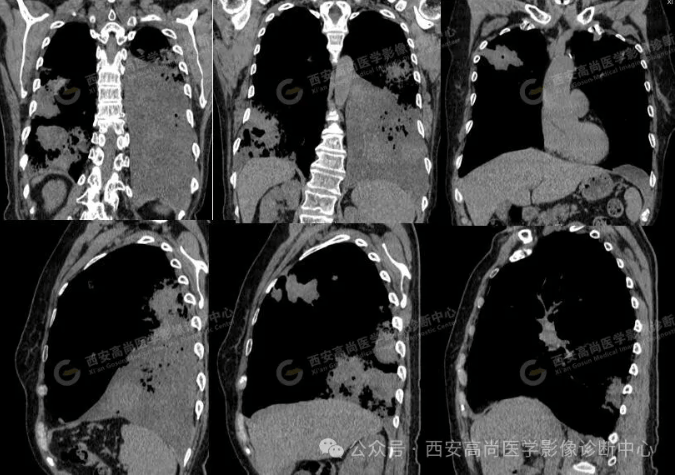

pet/ct病例—肺粘液腺癌,历经3年余终确诊【西安高尚医学影像诊断中心